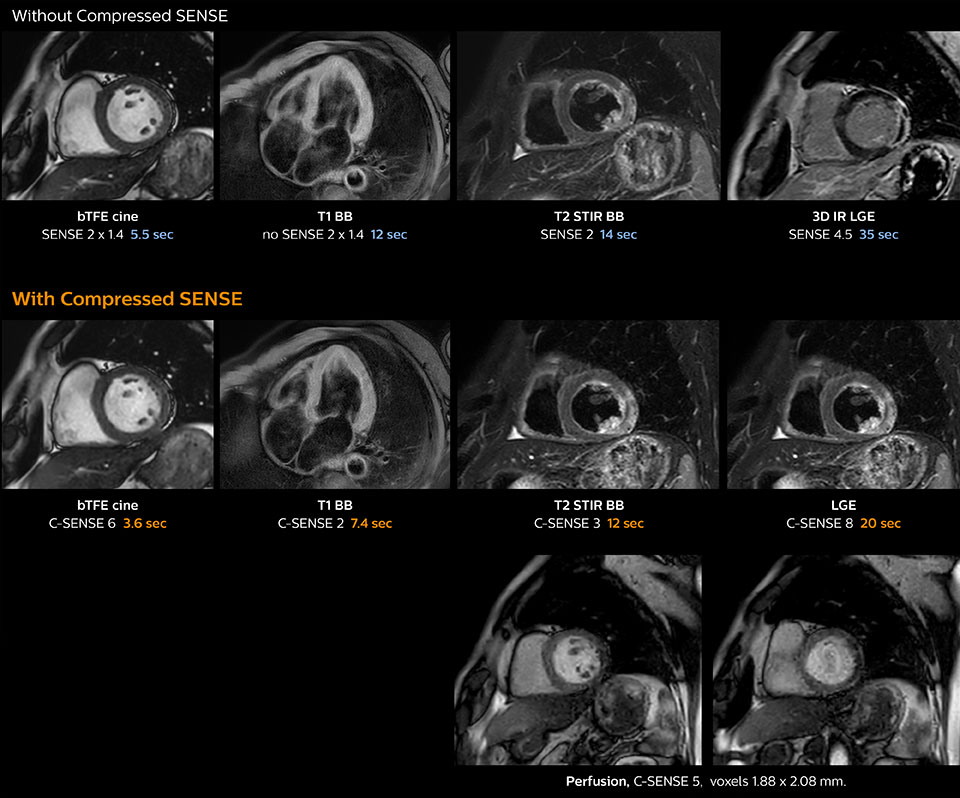

Faster1 cardiac imaging with fewer or shorter breath holds

“Compressed SENSE has now been implemented in all cardiac exams. Thanks to the acceleration, fewer breath holds are now needed, or breath hold times are shortened. This reduces the burden of the exam for cardiac patients, without affecting the quality of information required for cardiac function analyses,” he says. “Because it’s easier for patients to comply with the breath hold times” “In our previous cardiac cine sequence, we were acquiring two slices during one breath hold. With Compressed SENSE, we increased this to four slices per breath hold. It is also possible to shorten scanning time using a C-SENSE factor 6 without sacrificing image quality.”

Dr. Koshi Miyake, cardiologist, explains that scanning of patients with cardiac arrhythmia can be challenging, as scanning times can become very long due to the varying heart rate. So his most important motive to implement Compressed SENSE in cardiac MRI exams was to reduce the burden of breath holds for the patient, while maintaining high image quality. He hopes this can also help to reduce motion caused by the difficulty for patients to hold their breath.

“In cardiac MR we can now increase from two to four slices per breath hold”

Making Cardiac MR faster and easier for patients

“In cardiac MR fewer breath holds are now needed, or breath hold times are shortened”

“Typically, in scans with high contrast, such as 2D balanced TFE cine, a quite high C-SENSE factor may be used. When we tried a higher C-SENSE factor, we saw still no significant influence on cardiac ejection fraction, but 2D image quality started to decline. For coronary imaging, we use a C-SENSE factor of 3 in 3D balanced TFE, or even up to 4 when contrast is high.”

Cardiac MRI of acute myocardial infarction (AMI) w/wo Compressed SENSE

These images of a patient with acute myocardial infarction images were acquired on Ingenia 1.5T with and without Compressed SENSE.